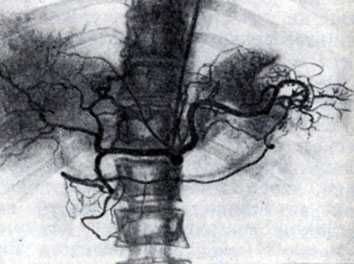

Рис. 3. Концевая ангиопульмонография. Катетер (виден под ключицей, вдоль позвоночника и в области сердца) введен в верхнесегментарную артерию верхней зоны правого легкого. Видны концевые артериальные разветвления. Контрастированы пути венозного оттока данного сегмента

Селективная ангиопульмонография позволяет одновременно измерять давление в полостях сердца и легочного ствола и определять степень насыщения крови кислородом. При концевой пнгиопульмонографии катетер вводят в одну из сегментарных ветвей легочной артерии (рис. 3),после чего инъецируют 5—8 мл контрастного вещества. Кроме описанных методик, ангиопульмонография может быть выполнена путем чрескожной пункции бедренной или подключичной вены по способу Сельдингера (с последующим введением зонда).